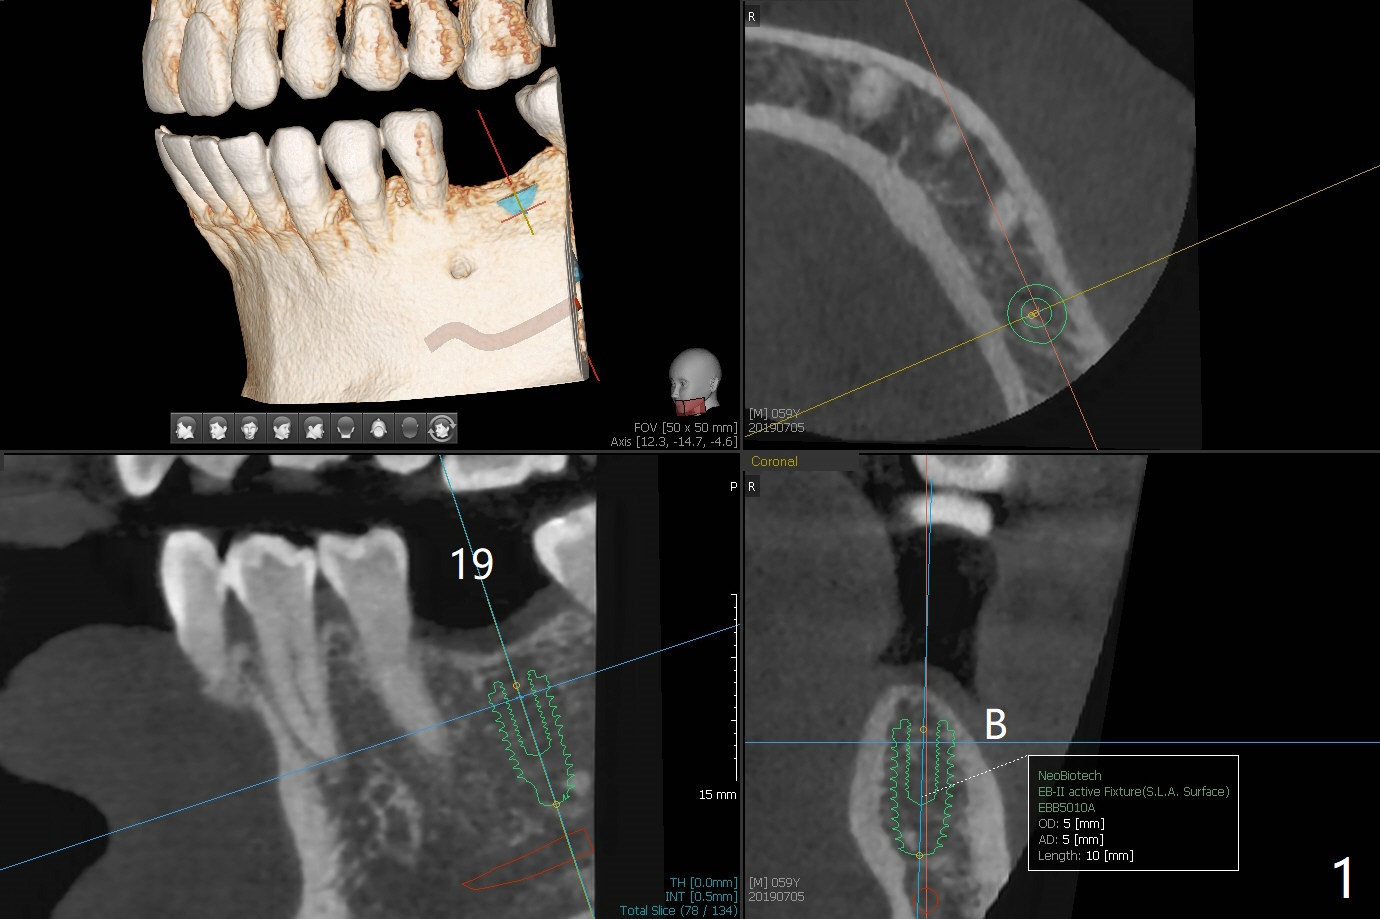

5x5 cm Field of View

A 59-year-old man has lost the tooth #19 for 30-40 years. Although the tooth #14 has supraerupted for ~ 2mm, there is enough vertical space for restoration (Fig.1), probably related to vertical bone loss. Use tissue-level implant (4.5x14 mm) to reduce screw loosening. Prepare a 4x5 or 3 mm unipost preferably with a precut groove to hold periodontal dressing in place. Return to Lower Molar Immediate Implant, Trajectory II Xin Wei, DDS, PhD, MS 1st edition 07/05/2019, last revision 08/13/2019